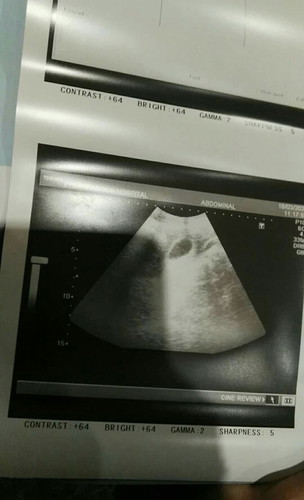

8w+2 ไปอัตราซาวแล้วเป็นอย่างงี้ อยากรู้ว่าเป็นท้องลม รึท้องนอกมดลูกค่ะ หมอนัดซาวอีกที8.เม.ย